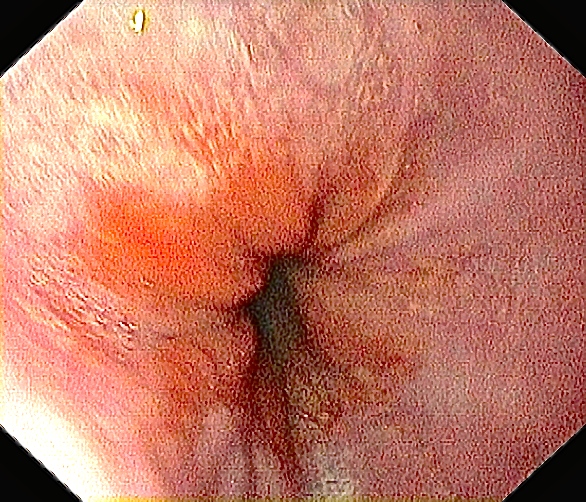

Inngang til tolvfingertarmen. Salvador Dali – go home! 🙂

Ved tolvfingertarmen kommer galle ut feil vei. Rene rundkjøringa 🙂